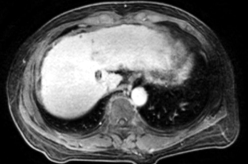

Ø 术前影像学检查

肝 S2 段及肝 S4 段见类圆形 T1WI 低、T2WI-SPAIR/DWI/ADC 高信号,较大者长径

约 10mm,界清。

动脉期

静脉期